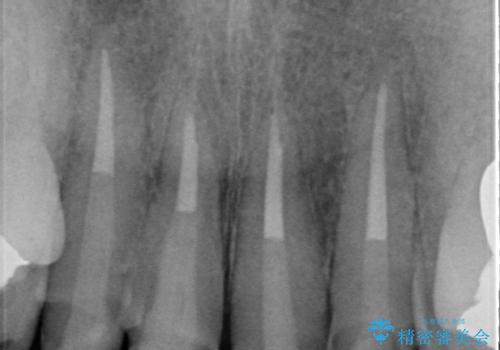

- 20年前に治療した前歯の劣化・審美障害の改善を求めて来院されました。

クラウンを除去し審美的なジルコニアクラウンによる補綴の再作製計画を立案します。

クラウンの適合について

クラウンと支台の適合が悪いと内部に汚れがたまり虫歯の再発・審美性の障害・口臭の発生リスク方あまります。